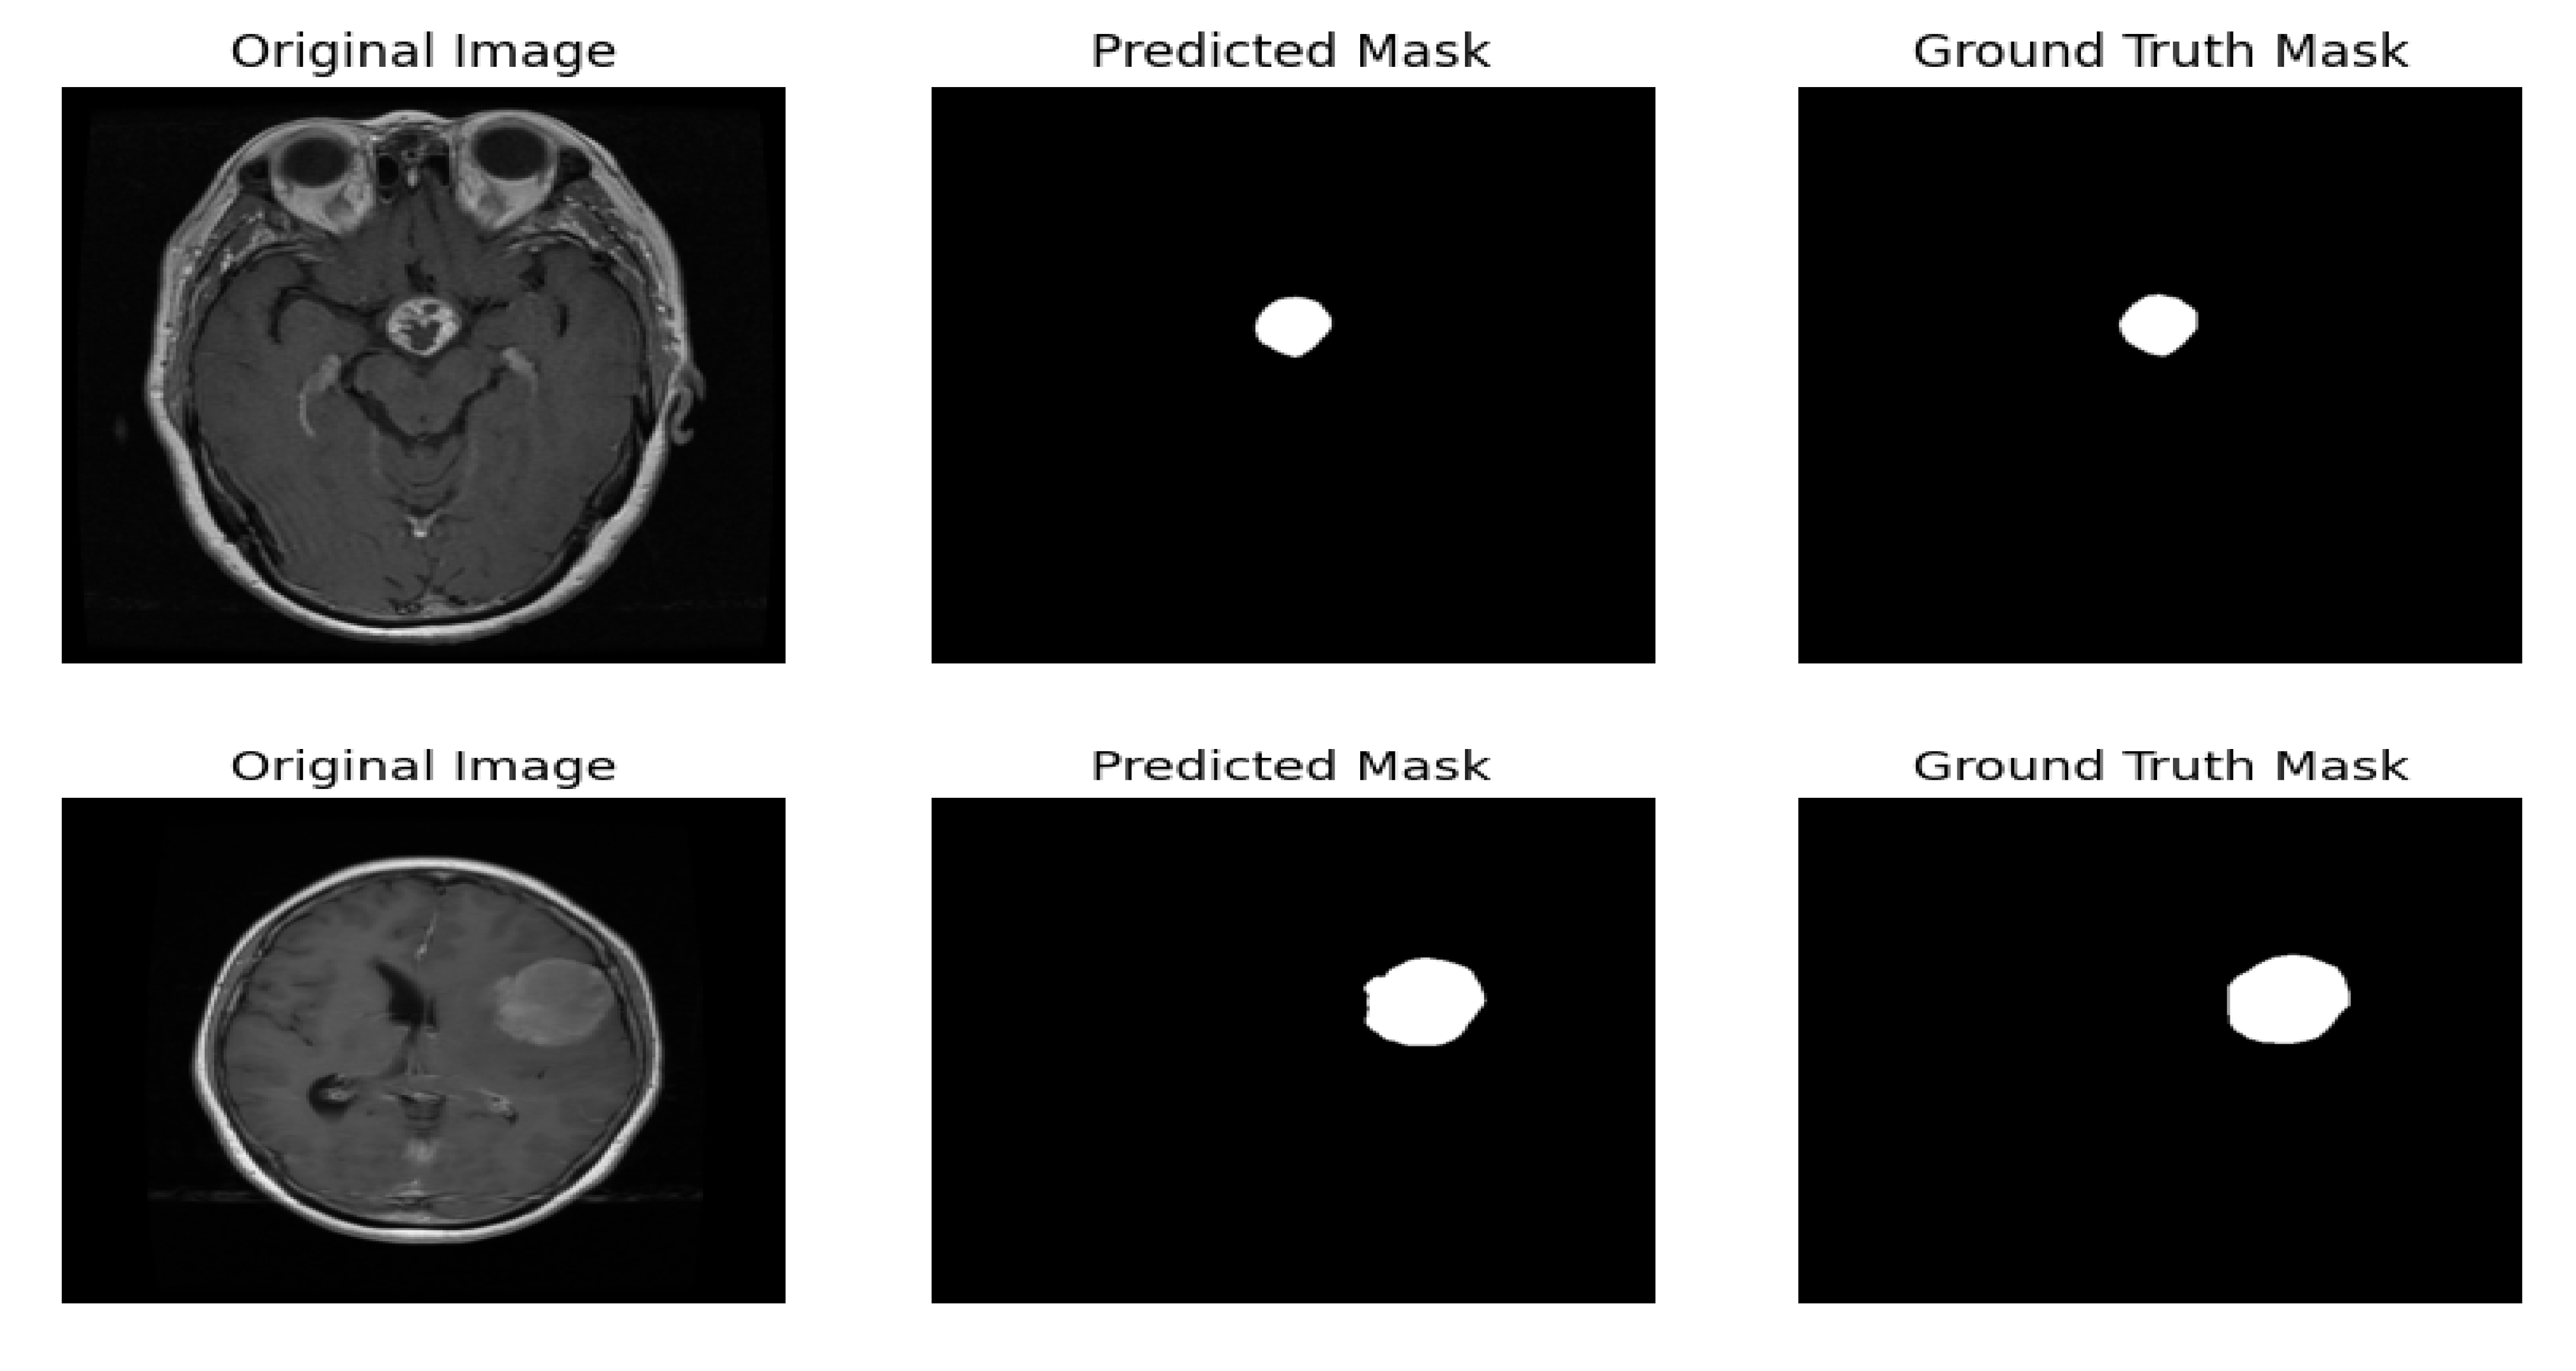

4.5. Results of the Hybrid Proposed Model

The YOLOv12–SAM 2 framework was evaluated by comparing the predicted segmentation masks with the corresponding ground truth masks. In Fig. (8), several test cases are presented to illustrate the model’s performance in segmenting brain tumours. The figure shows that the predicted masks closely match the ground truth masks, indicating that our system can accurately and effectively segment brain tumors.

Some test cases of ground truth mask vs. predicted mask.